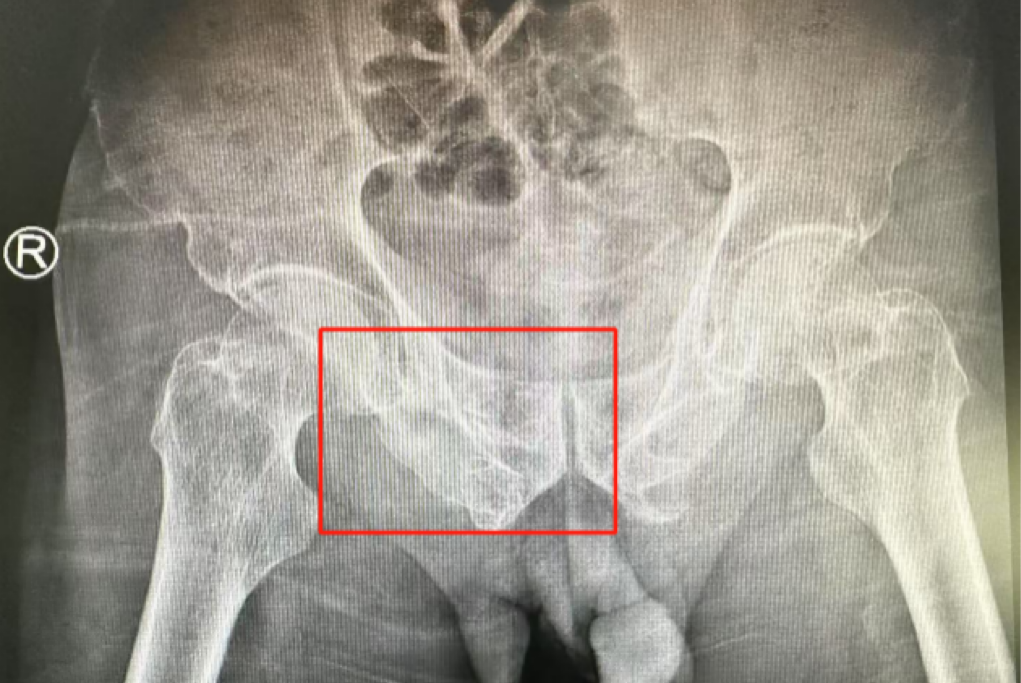

術(shù)前影像學(xué)顯示,患者的左側(cè)骶骨骨折,右側(cè)恥骨骨折、髂骨骨折,骨盆骨折分型為C型,老年脆性骨盆骨折分型為IV型,是極度不穩(wěn)定型的前環(huán)骨折和雙側(cè)后環(huán)骨折。所幸沒有明顯的骨盆出血或內(nèi)臟損傷的表現(xiàn)。

術(shù)后第二天,醫(yī)生團(tuán)隊(duì)復(fù)查X片顯示螺釘植入位置非常滿意,骨折基本達(dá)到穩(wěn)定復(fù)位,同時(shí),復(fù)查的全血細(xì)胞計(jì)數(shù)中,血紅蛋白指數(shù)為102g/L。術(shù)后第三天,在智能骨科病房護(hù)理團(tuán)隊(duì)及康復(fù)師的指導(dǎo)和護(hù)理下,王大爺可以坐立在床上。術(shù)后第四天,王大爺迎來了出院日,“得虧有了這么先進(jìn)的醫(yī)療技術(shù),讓我還能下地行走,謝謝你們!”

螺釘植入位置非常滿意

王大爺身體恢復(fù)良好